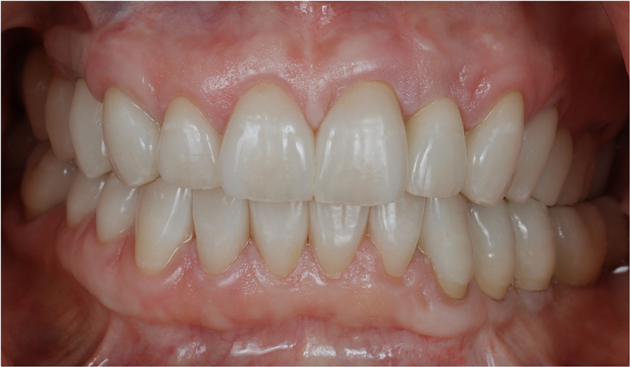

Figure 26 The healthy periodontal and dental implant foundation and gingival symmetry set the framework for the completion of the lithium-disilicate all-ceramic restorations.

Figure 26

Figure 27 The healthy periodontal and dental implant foundation and gingival symmetry set the framework for the completion of the lithium-disilicate all-ceramic restorations.

Figure 27

Once the healing was complete for the periodontal and dental implant procedures (Figure 22 and Figure 23), the final tooth preparations were completed and final impressions were made; records, including the electronic pantographic record, were then obtained. The treatment wax was used (Figure 24) to secure the patient’s approval of the esthetic design and to evaluate the esthetics and plan for the final prosthesis, including the cross-bite. The vertical dimension was raised, the facial anatomy was checked, and her speech and esthetics were checked by filming the patient and viewing facial profiles. Next, the implant abutments were made (Figure 25). In this case, metal–ceramic abutments were chosen; they were tried on before beginning the fabrication of the final restorations. These monolithic ceramic materials use lithium disilicate, which can result in a restoration with excellent biomechanical and esthetic properties (Figure 26 and Figure 27). The restorations were observed; the radiographs show the implants placed in the regenerated bone (Figure 28).